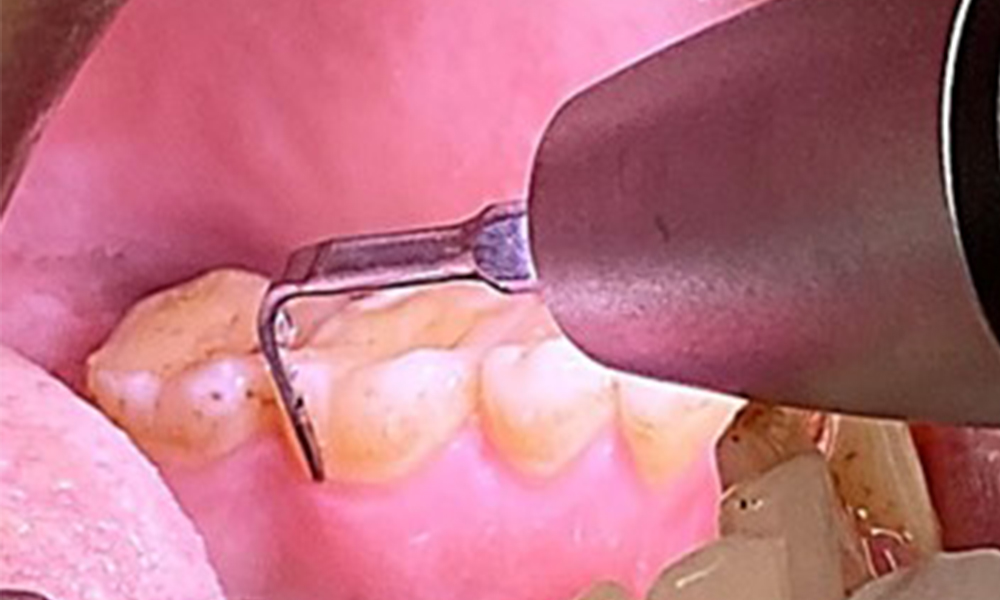

Pocket probing (BOP) with depiction of tooth 36 lingual

Fig. 7 Pocket probing (BOP) with depiction of tooth 36 lingual, © Dr R. Krapf

Due to the otherwise favourable general medical condition, the needs determined during the intraoral examination will be decisive for their treatment. It will be essential to periodically determine the probing depths. Gingival bleeding decreases in smokers, which is why the clinical diagnosis of periodontitis can only be made by probing (Fig. 7). Placing exclusive focus on the determination of bleeding indices may obscure existing periodontitis or gingivitis. (5)